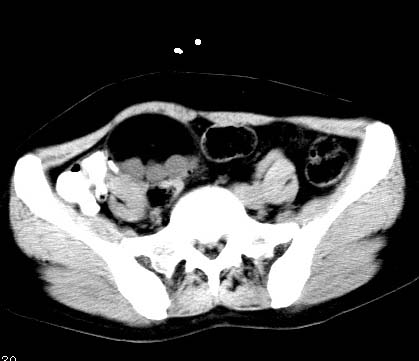

女性 病人 44岁 盆腔 下腹部痛1天!

盆腔内低密度为主混杂等密度及少许囊样与班状钙化影,如果做了肠道准备就好了。支持畸胎瘤。当然做mri会更好